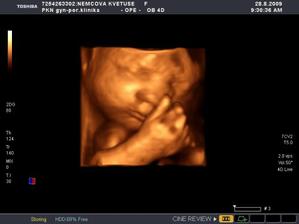

Nová naděje. Bohužel to bylo opět stejné, jako již dvakrát předtím. Třetí revize, třetí ztráta naděje. Jsem po laparoskopii a hysteroskopii a čekáme na výsledky imunologie v Plzni. Pak se uvidí co dál. V únoru 2009 nám v Sanusu doporučili ještě dva měsíce domácího snažení. Tak jsme se snažili a nyní napjatě sledujeme čárku. HCG nám krásně stoupá, 20. den po ovulaci je 2066. Máme 1. fotku dutinky. Přes nejrůznější potíže a patnáctidenní hospitalizaci nám miminko krásně roste. 22. dubna konečně po čtrnácti dnech ukázalo nosánek, máme nosní kůstku, NT je 2,0. Máme vše, co máme mít a rodiče se dnes poprvé společně dívali na ultrazvuk. Viděli mě i 4D, to koukali. Odnesli si video a teď na něj pořád koukají. Další kontrola náš čeká 5. května, opět ultrazvuk, triple testy a poradna. Trošku změna situace, mamka se mnou leží od 27. dubna v nemocnici, ale já ji dělám radost, rostu, 16.6. už vážím 360 gramů a od 5.6. ji kopu a ona o tom ví. Od 10. 6. se nám začal malinko měnit nález až jsme museli 10. 7., gr. h. 24+2 na cerclage, potom jsme měli zánět ledvin a astmatický záchvat. Pořád mamce tvrdlo břicho, tak se bez infuzí neobejde. 18. 7. se ještě objevilo krvácení, ale nebylo to nic závažného, byli jsme na ultrazvuku a vážím 908 gramů. V pátek 24.7. se to zlepšilo a kapeme na nejnižší rychlost, hurá. Mamka zatím nesmí chodit, má to slíbeno na 2. září. Kapeme sice na nejvyšší rychlosti, ale na ultrazvuku 4.8. mám odhad 1280 gramů. Dne 18.8. jsme byli na ultrazvuku a mám odhad 1750 gramů, mám trochu víc plodové vody a tak si tam plavu jako v bazénku. Dne 28.8. jsme byli s mamkou zase na ultrazvuku, vážím už 1950 gramů, mám udělaný krásný 3D fotečky, vody už nemám tolik moc, tak je mamka ráda. Jen se nám zase zkrátil čípek, už mě tam drží jen steh a 13 mm, ale držím mamce pěstičky, aby jsme vydrželi. No a taky si musím zvykat, mamka totiž má už dovoleno chodit na wc, a já jsem byl zvyklej, že pořád leží. Je sice z toho unavená, ale šťastná. Já jsem jí ještě udělal radost, že jsem se přetočil hlavičkou dolů. Dne 1.9. se mi konečně podařilo zbavit se té nitě, co tam mamka měla. Všichni jsou překvapení, jak se to mohlo stát, ale steh je pryč. Dne 10. 9. jsme s mamkou byli zase na ultrazvuku, vážím 2368 gramů (33+1). Hrdlo máme sice jen 9 mm, ale já se tam ještě udržím! Plodové vody mám už akorát, mamce klesly jaterní testy, žlučové kyseliny jsou v normě, tak má radost. Tak dnes 17. 9. jsem se byl zase vážit, mám 2517 gramů. Hrdlo má mamka jen 6,7 mm s obrovitým funnelingem, ale pořád drží. Denně mi točí monitory, mám je vzorné a pořád nemůžu přijít na to, jak ty sondy odkopnout. 26.9. pustil pan doktor mamku na propustku, byla poprvé 12 hodin mimo nemocnici, byli jsme na zahradě, grilovali jsme a já jsem babičce, dědečkovi a strejdovi předváděl, jak umím krásně kopat. Mamka byla moc šťastná. Večer se vrátila do nemocnice, dala si po 23. hodině sprchu a když usínala, tak jsem ji hodně překvapil, vypustil jsem svůj bazén. A tak se nešlo spinkat, ale na porodní sál. Šlo to pěkně a přesně ve 4.00 hodin jsem se narodil za skvělé asistence mého tatínka, který mamince na sále moc pomáhal. Vážím 2740 gramů a měřím 50 cm. Dosáhl jsem gestačního stáří 35+4. Rodiče a velká spousta lidí kolem ze mě mají velikánskou radost. Trošku jsem odmítal v inkubátoru dýchat, tak mě 1 den pomáhal CPAP. Večer mi ho vzali a teď už se snažím sám. mamka za mnou chodí a já jsem rád, když ji vídím. Dnes jsem na ni poprvé otevřel očička, snažím se papat, dnes už ze stříkačky. Tatínek je ze mě unešenej a já jsem rád, když mě přijde pohladit a vyfotit.